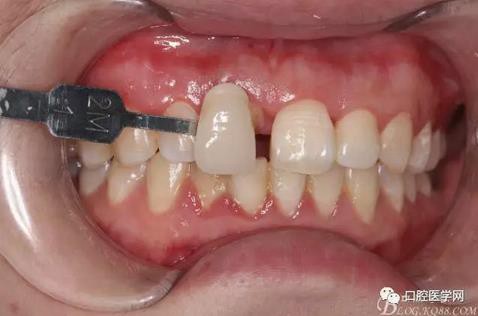

牙冠延長術(shù)后6周復(fù)診牙齦齦緣形態(tài)恢復(fù)良好,齦乳頭有些欠缺,患者著急永久修復(fù)。

比色

戴牙